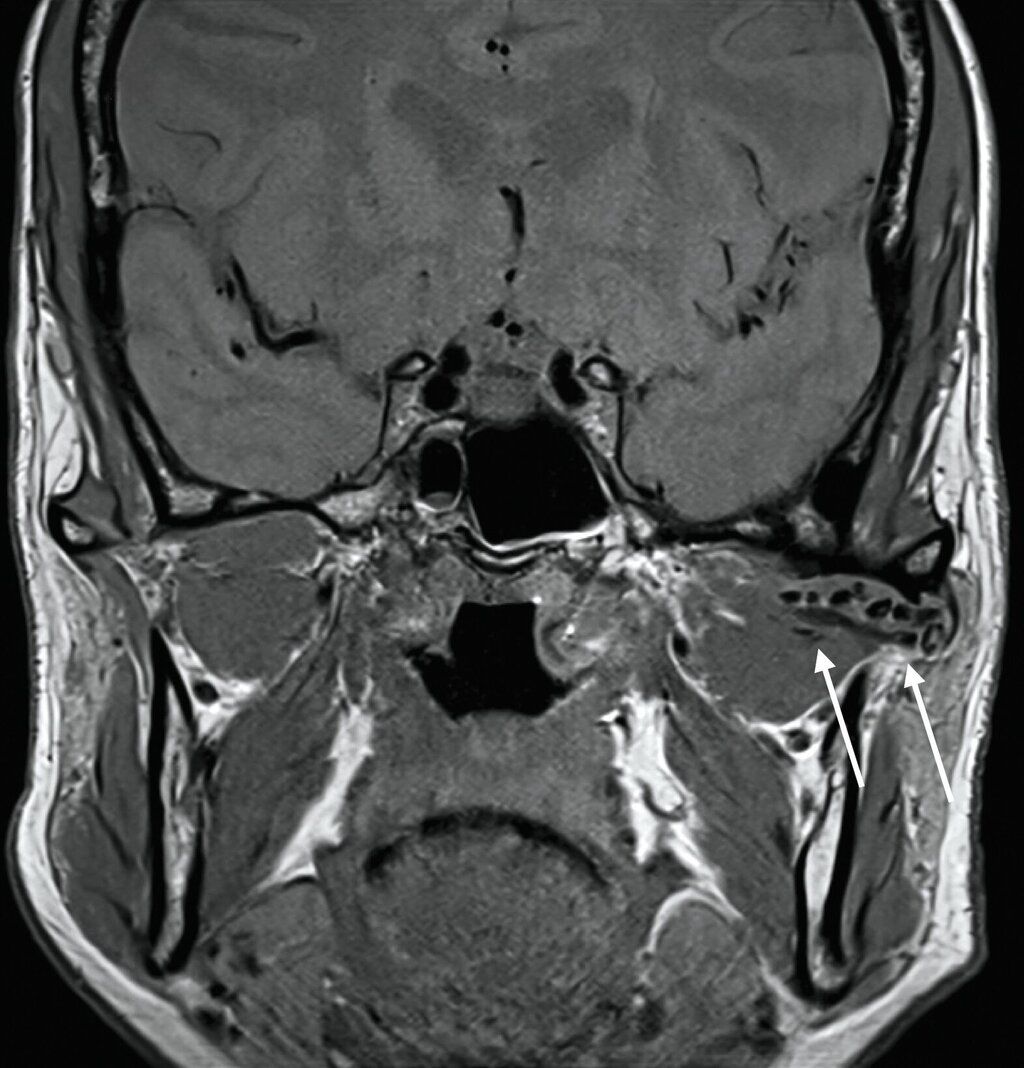

Klinisch zeigte sich kein Hinweis auf eine Myopathie der Kaumuskulatur. Zudem waren weder eine Mundöffnungsbehinderung noch ein Kiefergelenkgeräusch detektierbar. In Anbetracht der klinischen und der radiologischen Verdachtsdiagnose wurde eine Magnetresonanztomografie durchgeführt (Abbildung 2), die eine deutliche Flüssigkeitskollektion zirkulär im Bereich des linken Kiefergelenks mit multiplen, a. e. hyalinen Fragmenten sichtbar macht.